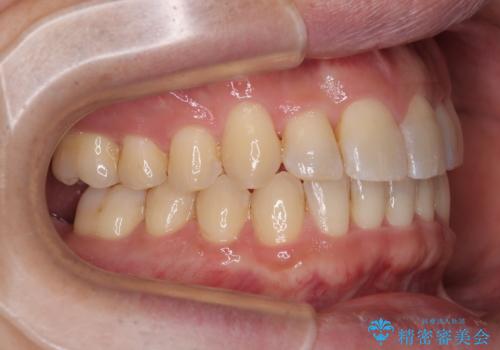

- クリアブラケット

- 1年1ヶ月

- 上下前歯のデコボコを気にして来院された患者様です。

ワイヤー矯正でもマウスピース矯正でも可能でしたが、短期間で、自身の手を煩わせることなく治療を行いたいとのことで、ワイヤー装置にて矯正治療を行うこととしました。

上顎前歯の舌側転位が顕著であったため、治療期間が長くなると思われましたが、僅か1年で無事に終えることができました。